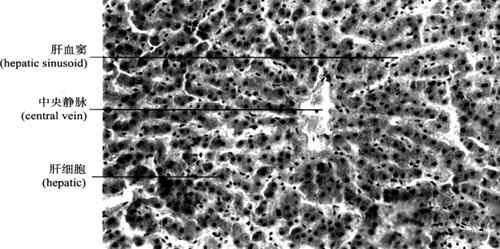

2.肝的组织结构 肝表面有致密结缔组织被膜(也称Glisson囊)。在肝门处,此结缔组织纤维囊特别发达,并包绕门静脉、肝动脉和肝管的分支形成Glisson鞘,进入肝内,成为Glisson系统,将肝实质分隔成许多肝小叶。肝小叶(hepatic lobule)是肝脏的结构和功能单位,呈多面形棱柱体,长约2mm,宽约1mm。其长轴中央有肝静脉的终末支中央静脉(central vein)穿过。成人肝脏约有50~100万个肝小叶。肝小叶主要结构为肝细胞和肝血窦。肝细胞以中央静脉为中心呈放射状排列,单排肝细胞组成立体板状结构,称肝板(hepatic plate)(图9-40),相邻肝板互相吻合成网状;肝血窦位于肝板之间,通过肝板上的孔洞互相通连;相邻肝细胞接触面,质膜内陷成沟,两沟对合成微细管道,称胆小管(bile canaliculi),以盲端起始于中央静脉附近,在肝板内互相连接成网。肝细胞分泌的胆汁经胆小管汇入肝小叶周边的小叶间胆管(interlobularbile ducts)。在肝组织切片中,肝板的断面呈索状,称肝索(hepatic cord)(图9-41)。

图9-41 肝脏(200×)

(1)肝细胞(hepatocyte):呈多面形,核大而圆,位于中央,异染色质少而分散,核仁清楚,表明细胞合成蛋白质的功能活跃。肝细胞内有各种细胞器及糖原、脂滴和色素等内含物(图9-42)。

(2)肝血窦(hepatic sinusoid):是位于肝板之间的窦状毛细血管,来自小叶间动、静脉终末支的血液经其汇入中央静脉。肝血窦壁由一层有孔内皮细胞组成,通透性较大,有利于肝细胞与血液间物质交换。窦内有许多形状不规则的巨噬细胞(macrophase),称枯否细胞(Kupffer cell)(图9-43),具有变形运动和吞噬功能,可清除血液内异物、细菌、衰老的红细胞。由于其数量大,分布在血窦内重要部位,构成机体重要防御屏障,尤其在抗肝癌作用方面受到重视。体外培养的Kupffer细胞受肿瘤抗原刺激后,体积增大,Fc受体增加,与肿瘤细胞贴附力增强,细胞分泌肿瘤坏死因子(TNF)增多,可杀伤和破坏肿瘤细胞,而不影响正常细胞。

图9-43 肝索与肝血窦(400×)